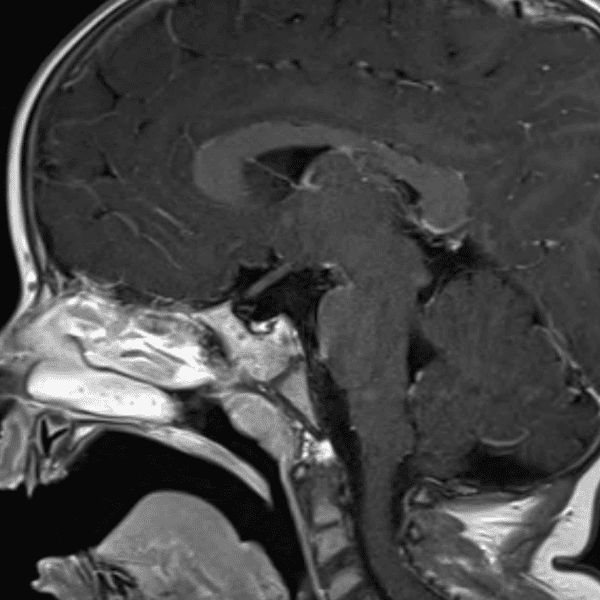

๋‹น์ง ์‹œ ํ”ํžˆ ๋ณผ ์ˆ˜ ์žˆ๋Š” ์‚ฌ๋ก€์˜ ์ „ํ˜•์ ์ธ ์˜ˆ๋ฅผ ํฌํ•จํ•ฉ๋‹ˆ๋‹ค.

39 ์‚ฌ๋ก€